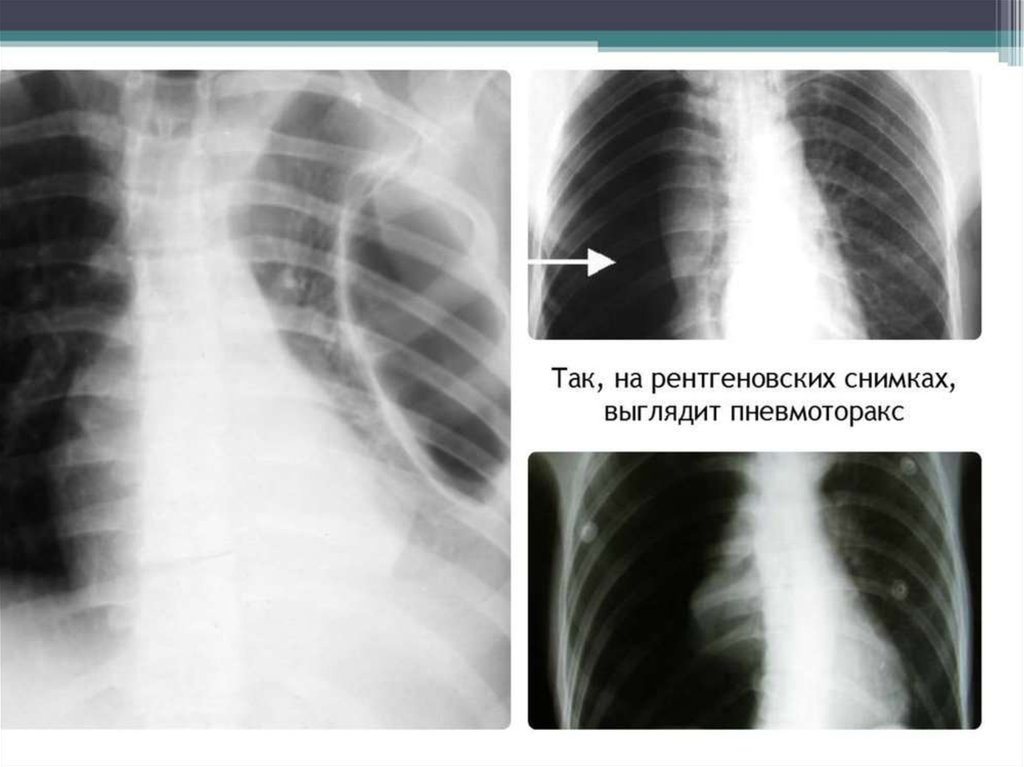

31. Пневмотаркс

Спонтанды пневмоторакс